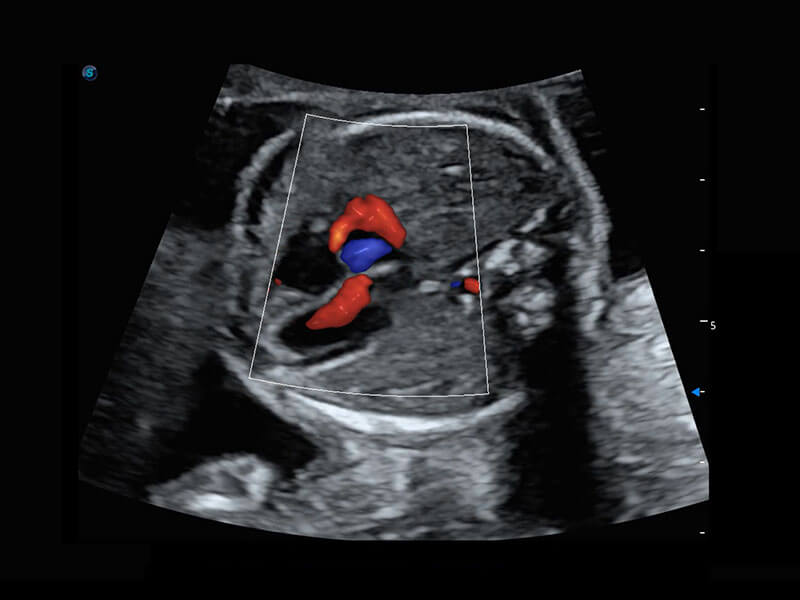

P60搭载一系列胎儿心脏成像技术,实现精细的胎儿心脏评估。

四腔心血流

胎心容积成像